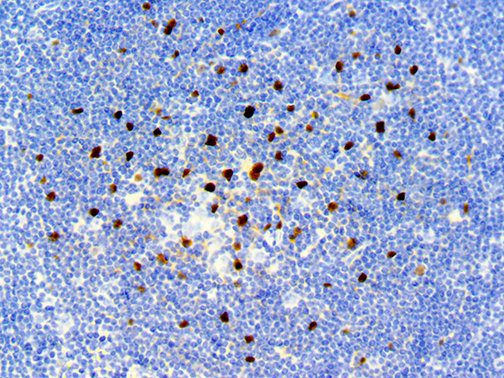

It is the ICU physician who is most likely to witness one of the deadliest manifestations of the abnormal immunological response, the cytokine storm syndrome (CSS). This response is also referred to by some as the cytokine release syndrome (CRS). CSS is characterized by continuous activation and expansion of macrophage and lymphocyte populations, which secrete large amounts of cytokines, causing the cytokine storm. This massive cytokine release is akin to hemophagocytic lymphohistiocytosis (HLH) disease, a syndrome characterized by initial unchecked and persistent activation of cytotoxic T lymphocytes and NK cells.

Clinical and laboratory manifestations of HLH include fever, enlarged liver and/or spleen, neurologic dysfunction, coagulopathy, liver dysfunction, cytopenias (i.e., low levels of erythrocytes, leukocytes, and/or platelets), hypertriglyceridemia, hyperferritinemia, hemophagocytosis, and eventually diminished NK cell activity as the immune system becomes progressively paralyzed. HLH can be familial (primary HLH) or secondary to another disease process (sHLH), such as rheumatic disease, in which it is referred to as macrophage activation syndrome (MAS, characterized by elevated ferritin).